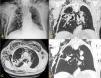

Presentamos el caso de un varón de 74 años con adenocarcinoma de pulmón (pT1aN0M0) en el lóbulo superior derecho (LSD), tratado mediante resección segmentaria y radioterapia (RT) posquirúrgica, en el que se detectó recidiva tumoral local durante el seguimiento. Dada la alta comorbilidad, se decidió realizar termoablación con microondas (TM) guiada por TC. El procedimiento transcurrió sin incidencias y el paciente fue dado de alta. Sin embargo, una semana más tarde, acudió a Urgencias refiriendo sensación opresiva y dificultad respiratoria. A la exploración se encontraba eupneico y estable, con crepitación de partes blandas torácicas y voz bitonal. Se realizó una radiografía de tórax que mostró un marcado enfisema subcutáneo, sin signos de neumotórax (fig. 1A). En la TC de tórax se evidenció una cavitación pulmonar en el lecho de TM en comunicación con un bronquio para el LSD y con un gran lóculo de gas en la pared torácica, junto a extenso neumomediastino y enfisema subcutáneo (fig. 1B-D), hallazgos compatibles con fístula bronquial (FB) y broncocutánea (FBC) desde la cavidad postermoablación. El paciente fue hospitalizado con monitorización y drenaje del enfisema, evolucionando favorablemente.

Radiografía de tórax, proyección PA (A). Extenso enfisema subcutáneo en pared torácica derecha y región supraclavicular y cervical, junto con neumomediastino (flechas). Masa mal delimitada en lóbulo superior derecho (asterisco), en aparente comunicación con un bronquio para dicho lóbulo (puntas de flecha). TC de tórax sin contraste intravenoso, ventana de parénquima pulmonar. Reconstrucciones multiplanares en plano coronal (B) y axial (C), con proyección de mínima intensidad (D). Se muestra con claridad la cavidad aérea rodeando la masa tratada (puntas de flecha en B y C), en comunicación con una rama bronquial para dicho lóbulo (punta de flecha en D), así como neumomediastino (flechas blancas) y extenso enfisema subcutáneo de predominio en pared costal derecha. Llama la atención un gran lóculo de gas en la pared torácica adyacente a la cavidad postermoablación, que sugiere la existencia de comunicación entre ambas cavidades (asterisco en C y D). También se observan signos de enfisema centrolobulillar de predominio en lóbulos superiores.